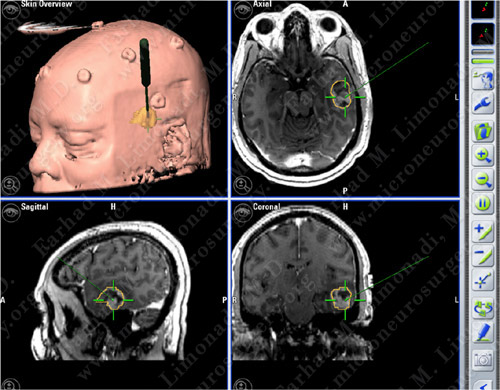

Computer Navigation

Computer navigation and stereotaxy utilized to map and localize the tumors (outlined in yellow) during surgery.